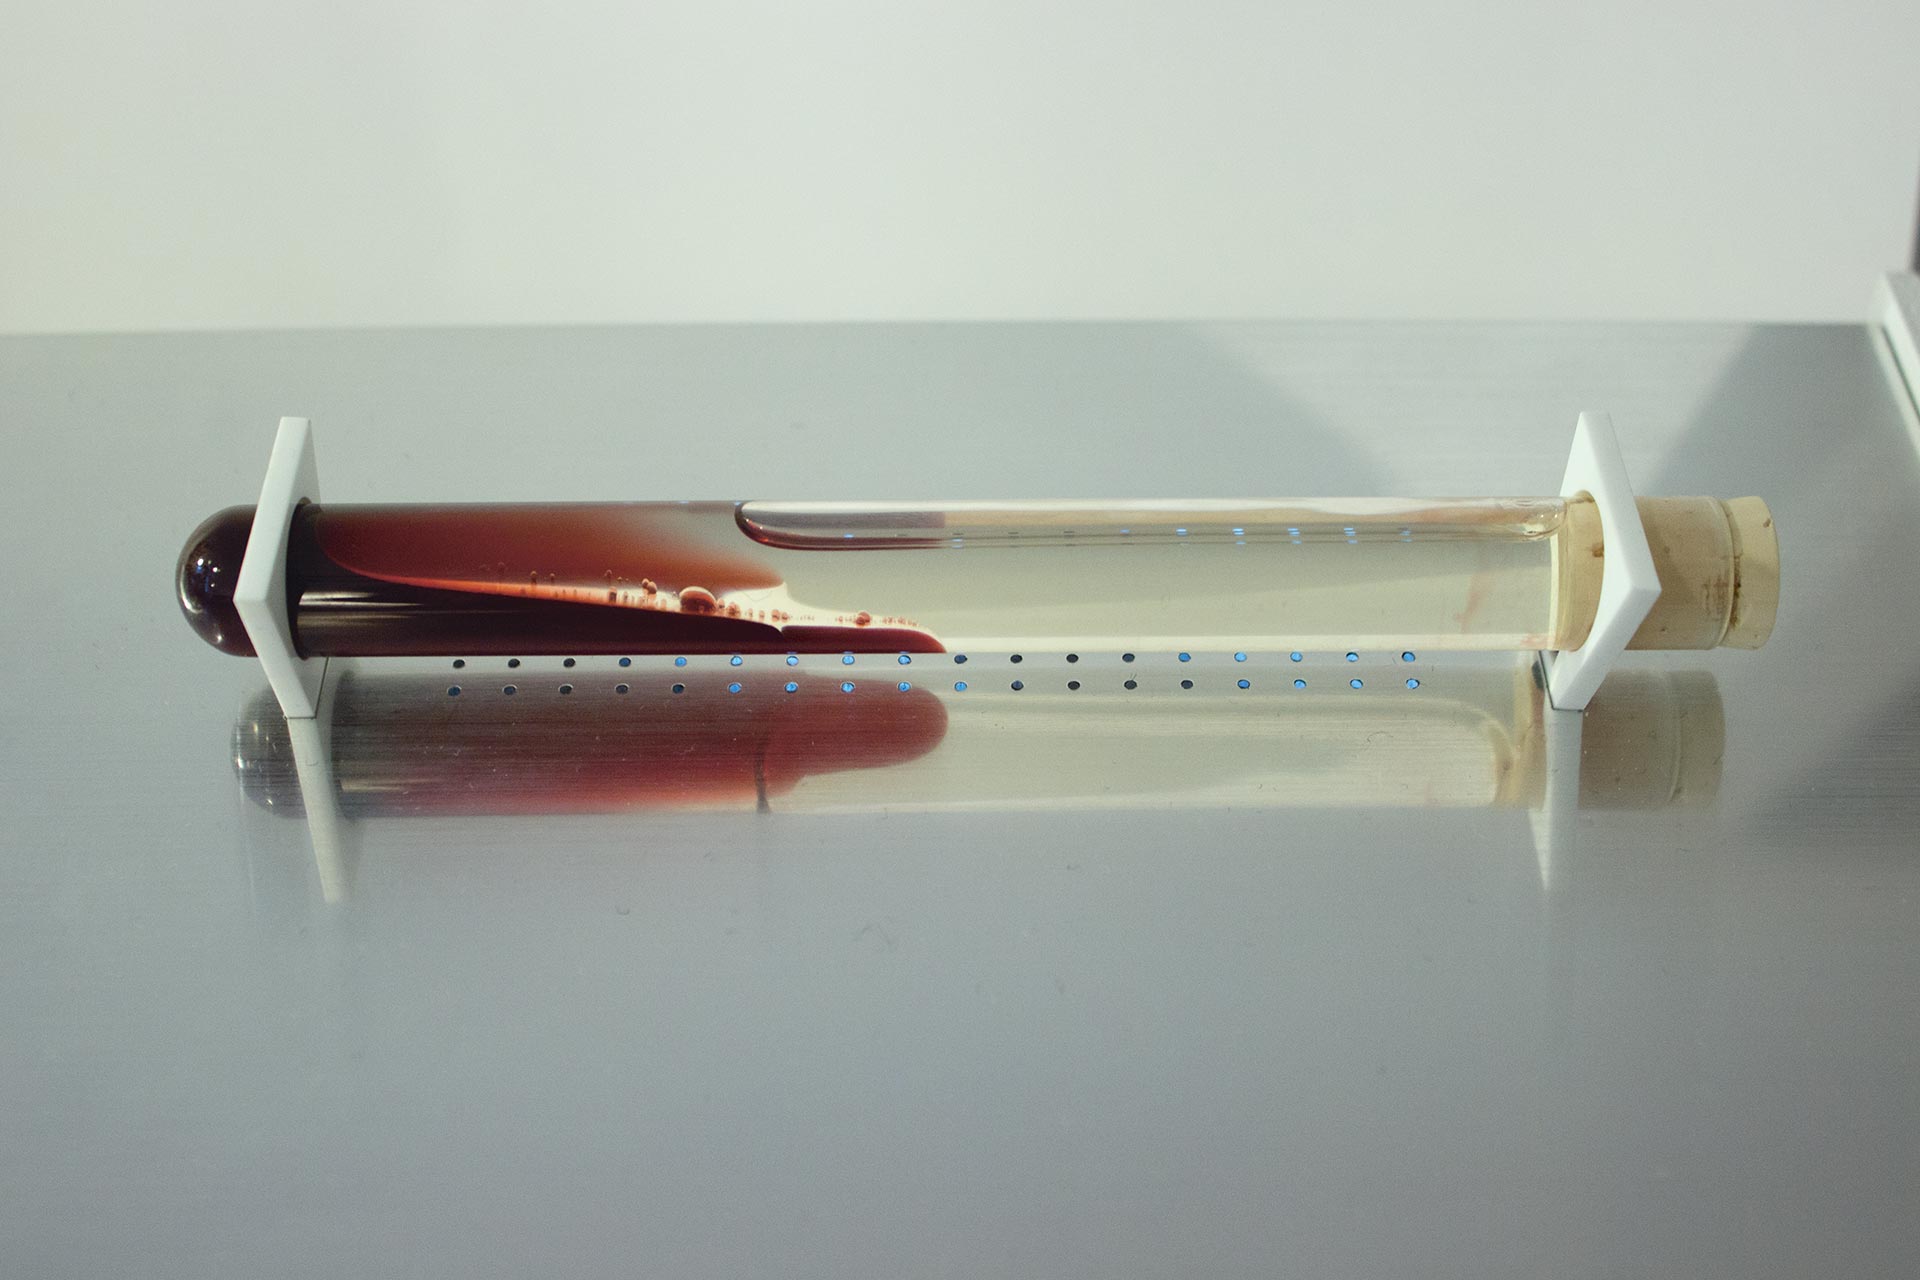

The Beauty of Oppositions

ID # 24661

Universität der Künste Berlin, DE

professors : Joachim Sauter, Jussi Angeslevä, Siegfried Zielinski

Stephan Sunder-Plassmann

contact :

www.stephansunderplassmann.com